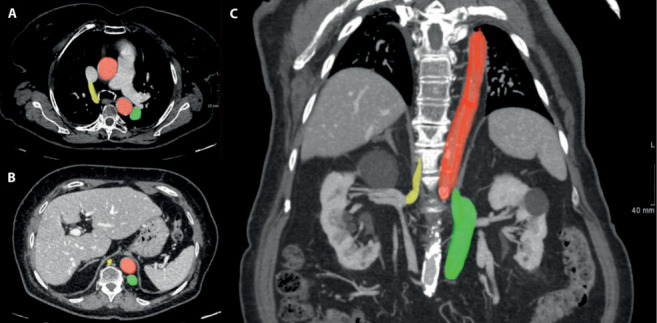

下腔静脉(IVC)中断伴奇静脉/半奇静脉延续是一种极不常见的先天性血管异常,可能存在多种变异。因此,在文献中找到相同的解剖学变体是具有挑战性的。我们报告了一例83岁女性患者的IVC中断伴半奇果和经肝持续的独特病例。该病例通过计算机断层扫描(CT)作为成像模式进行评估,采用多阶段方案,能够准确检测这种复杂的血管异常。本病例报告的目的不仅是介绍这一引人注目的病例,而且从IVC和奇静脉系统的解剖学和胚胎学出发,简要介绍IVC中断的类型,并讨论成像在检测血管异常中的价值。

Inferior vena cava (IVC) interruption with azygos/hemiazygos continuation is an extremely uncommon congenital vascular anomaly, which may present with multiple variants. As a result, it is challenging to find in the literature the same anatomical variant. We report a unique case of an interrupted IVC with hemiazygos and transhepatic continuation in an 83-year-old female patient. The case was evaluated by performing Computed Tomography (CT) as imaging modality, with a multiphase protocol, able to detect accurately this complex vascular anomaly. The purpose of this case report is not only to present this remarkable case but also to briefly show the types of interrupted IVC, starting from the anatomy and the embryology of the IVC and the azygos system, and to discuss the value of imaging in detecting the vascular anomaly.